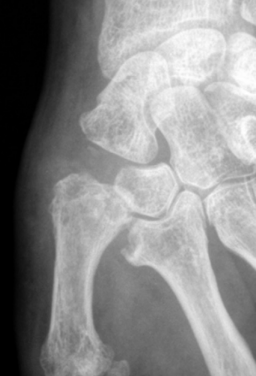

Trapézectomie et ligamentoplastie

L'ablation du trapèze et le comblement du vide par un tendon